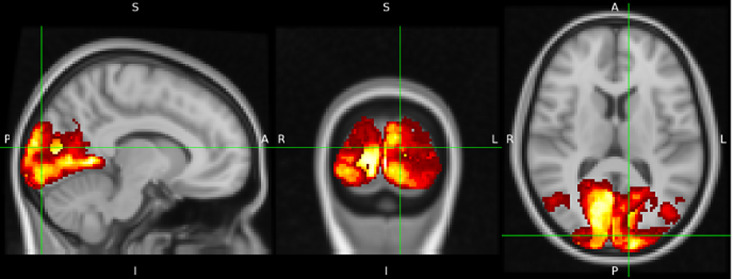

Introduction: This research is focused on early detection of Alzheimer's disease (AD) using a multiscale feature fusion framework, combining biomarkers from memory, vision, and speech regions extracted from magnetic resonance imaging and positron emission tomography images.

Methods: Using 2D gray level co-occurrence matrix (2D-GLCM) texture features, volume, standardized uptake value ratios (SUVR), and obesity from different neuroimaging modalities, the study applies various classifiers, demonstrating a feature importance analysis in each region of interest. The research employs four classifiers, namely linear support vector machine, linear discriminant analysis, logistic regression (LR), and logistic regression with stochastic gradient descent (LRSGD) classifiers, to determine feature importance, leading to subsequent validation using a probabilistic neural network classifier.

Results: The research highlights the critical role of brain texture features, particularly in memory regions, for AD detection. Significant sex-specific differences are observed, with males showing significance in texture features in memory regions, volume in vision regions, and SUVR in speech regions, while females exhibit significance in texture features in memory and speech regions, and SUVR in vision regions. Additionally, the study analyzes how obesity affects features used in AD prediction models, clarifying its effects on speech and vision regions, particularly brain volume.